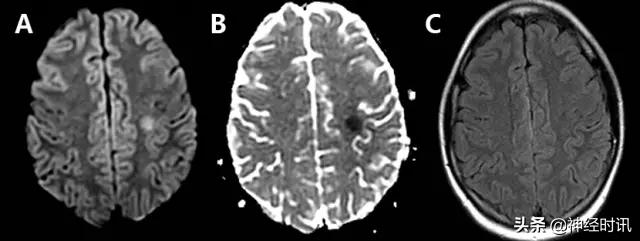

克雅氏病

克雅氏病(CJD)是由于朊蛋白错误折叠导致的快速进展性、传染性、致死性神经退行性疾病。DWI比FLAIR或T2WI更加敏感,并伴ADC降低。CJD患者有对称性基底节受累和对称性或非对称性皮层受累(图10)。

图10 一例48岁女性,精神状态改变、亚急性记忆减退伴步态异常1年,近期出现人格改变。MRI显示双侧基底节、丘脑、皮质弥散受限(A:DWI,B:ADC)和T2-FLAIR(C)高信号。患者被诊断为CJD。